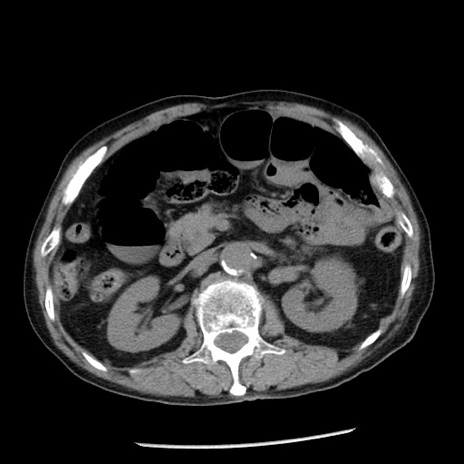

症例26(横断像)

【症例】80歳代男性

【主訴】嘔吐

【現病歴】昨晩2回嘔吐あり、今朝になっても嘔吐あり。来院。

【既往歴】胃潰瘍

【身体所見】意識清明、BT 37.6℃、BP 166/95mmHg、HR 100bpm、SpO2 97%、腹部:平坦・軟、腸蠕動音聴取良好、圧痛なし。

【データ】WBC 21900、CRP 1.46